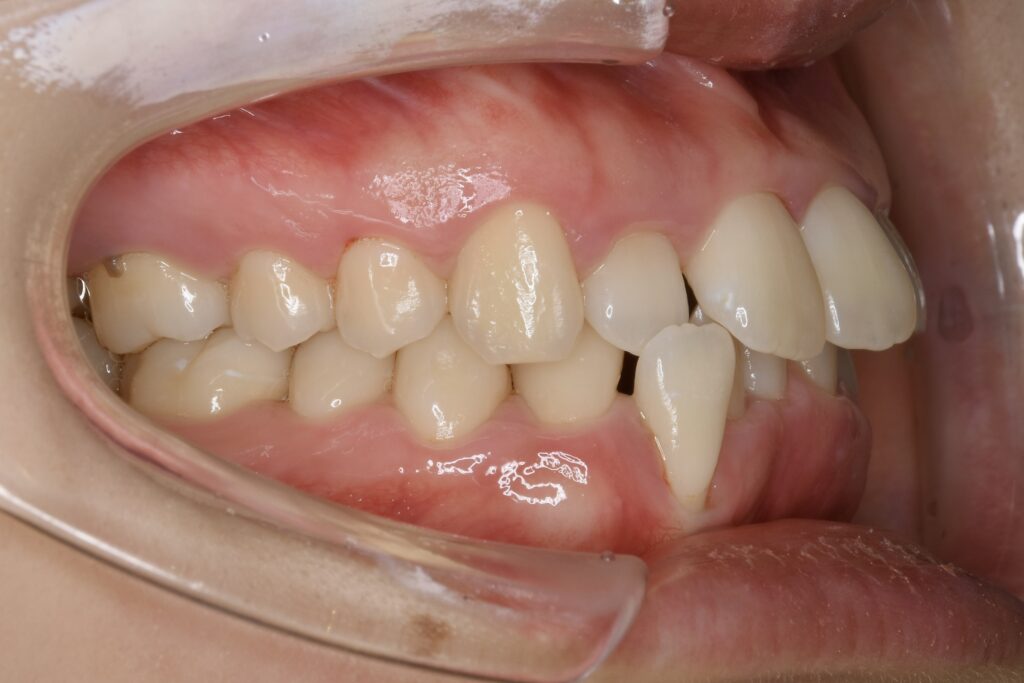

21歳 女性 治療期間:1年1ヶ月

叢生(ガタガタ)

マウスピース矯正装置(インビザライン)

非抜歯

BEFORE

AFTER

診断名・主な症状

叢生

治療内容

上下とも歯並びの横幅を広げながら、でこぼこを解消しました。

マウスピース矯正(インビザライン)

抜歯あり(智歯抜歯)

治療期間

1年1ヶ月

通院回数

10回

費用

85万円程度(税別)

リスク・副作用

痛み、歯肉退縮、歯根吸収、抜歯に伴う出血や腫れが生じることがあります。